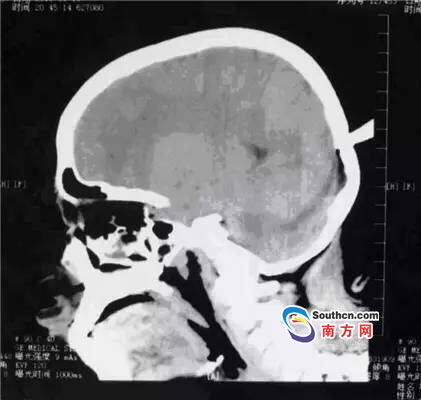

接到小玲受傷的消息,東莞市第三人民醫(yī)院急診科立即啟動了急癥危重患者搶救流程。急癥頭部CT顯示,飛鏢已穿透小玲的顱骨,并突破硬腦膜,情況非常兇險,小玲命懸一線。

此時,小玲也處于極度恐懼和不安中。醫(yī)生表示,必須及時手術(shù)取出異物、止血并妥善處理顱內(nèi)相關(guān)損傷,否則飛鏢將進一步損傷腦組織,引起二次傷害,甚至可能引發(fā)顱內(nèi)大出血。搶救刻不容緩,醫(yī)院神經(jīng)外科醫(yī)師立即與麻醉手術(shù)科聯(lián)系,開通綠色通道準(zhǔn)備急診手術(shù)。

開顱還是不開顱?這是擺在神經(jīng)外科醫(yī)生面前最重要的問題。此時的檢查結(jié)果無法判斷有無血管和腦組織的損傷,開顱手術(shù)可以直接看到損傷的情況,及時進行處理,但是如果飛鏢沒有損傷大血管,開顱的話就會造成比較大的創(chuàng)傷;不開顱手術(shù),手術(shù)的全過程造成的損傷就會減少,但是如果有大血管的損傷,不開顱直接拔出飛鏢,就不能及時進行止血和清創(chuàng)。